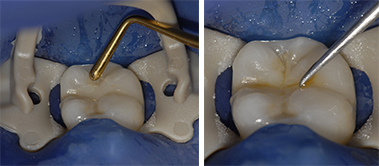

L’intégration esthétique des restaurations d’usage trans-vissées réalisées par CFAO est exceptionnelle. En effet ces restaurations monolithiques, par opposition aux restaurations céramo-métalliques pour lesquelles la céramique cosmétique doit être soutenue par l’infrastructure métallique, présentent une grande quantité de céramique surplombant le fût de vissage. Le comblement de ce fût par du téflon recouvert de composite permet de masquer totalement l’embase en titane et la vis de trans-fixation (Fig. 14 a, b et c).

Fig. 13 : Comblement du fût de vissage

13a : Mise en place de composite

13b : Maquillage des sillons

13c : Résultat final